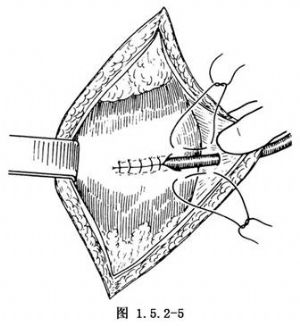

切口及显露手术野的步骤与荷包式胃造口术相同。胃造口部位应选择在胃前壁偏右侧,用不吸收线做一荷包缝合,于其中央切开胃壁,用导尿管经此切口插入胃腔并收紧结扎荷包缝合线(图1.5.2-4)按照胃的纵轴方向,沿导管两侧做胃壁浆肌层缝合,将导管包埋于浆肌层缝合的隧道中,长度约4~5cm(图1.5.2-5)。将导管从切口左侧腹壁的戳口拖出、沿导管四周的胃壁与腹膜缝合固定3或4针使造口处胃壁紧贴腹壁。最后将导管与皮肤固定并缝合切口(图1.5.2-6)。